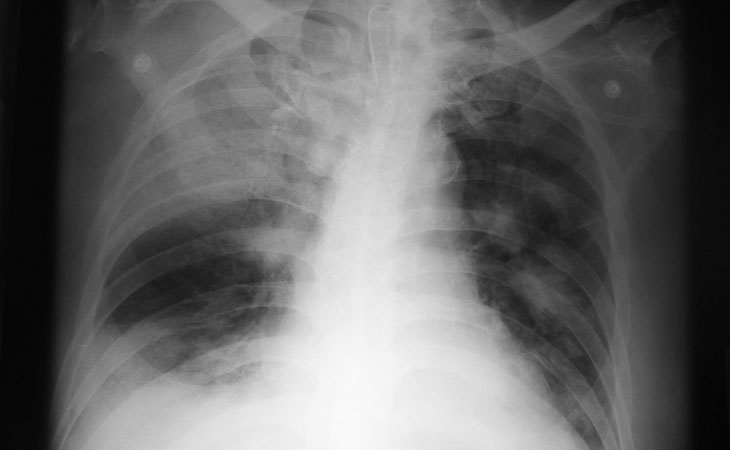

Pneumatocele

Un pneumatocele è una  raccolta aerea parenchimale polmonare, di aspetto cistico, secondaria a traumi bronchiali o ad infiammazioni in grado di determinare, con un meccanismo a valvola, la penetrazione di aria nel parenchima polmonare.